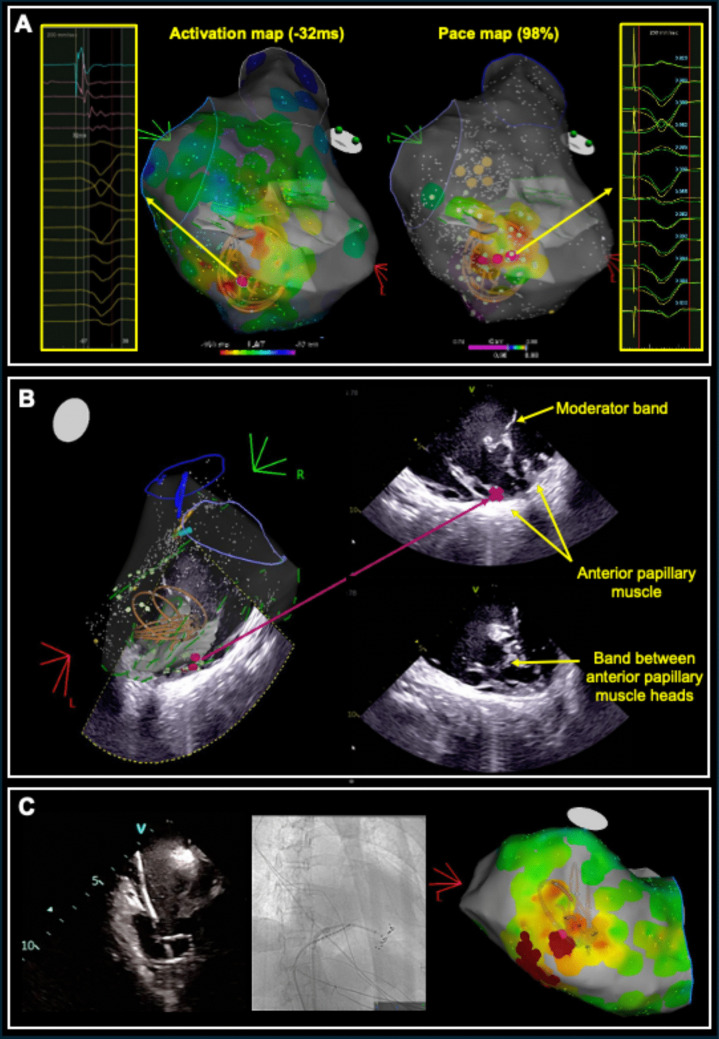

Introduction: Premature ventricular complexes (PVCs) from intracavitary structures, such as papillary muscles and the moderator band, can be challenging to treat. Pulsed field ablation (PFA) offers a novel strategy for treating these arrhythmias.

Methods: Between 2023 and 2024, three patients with intracavitary PVCs (two with PVC-mediated ventricular fibrillation) underwent PFA at a tertiary referral centre. Electroanatomic mapping was performed and, with intracardiac echocardiography (ICE) guidance, PFA was delivered using a pentaspline Farapulse catheter, with adjuvant radiofrequency (RF) ablation as needed.

Results: All patients had successful abolition of PVCs. PFA delivery was feasible and safe, with excellent success despite prior RF ablation failures though one patient required adjuvant RF ablation. The only complication was a persistent right bundle branch block (RBBB) after PFA delivery to the moderator band. Follow-up showed significant reductions in PVC burden and no further ventricular fibrillation (VF) episodes. The mean procedural duration was 153.67 ± 31.71 min, and the mean fluoroscopy time was 14.38 ± 6.74 min.